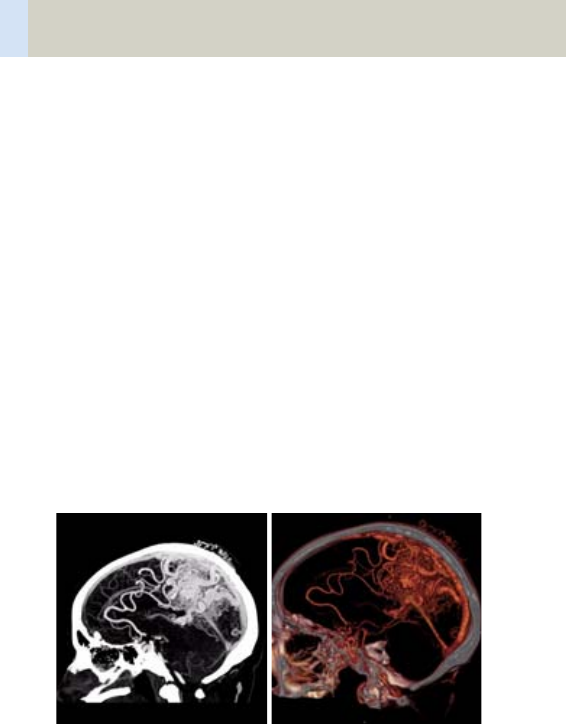

- HeadAngio/

HeadAngio06s 366

- HeadAngioVol 370

- ThorAngioVol 384

- Embolism/